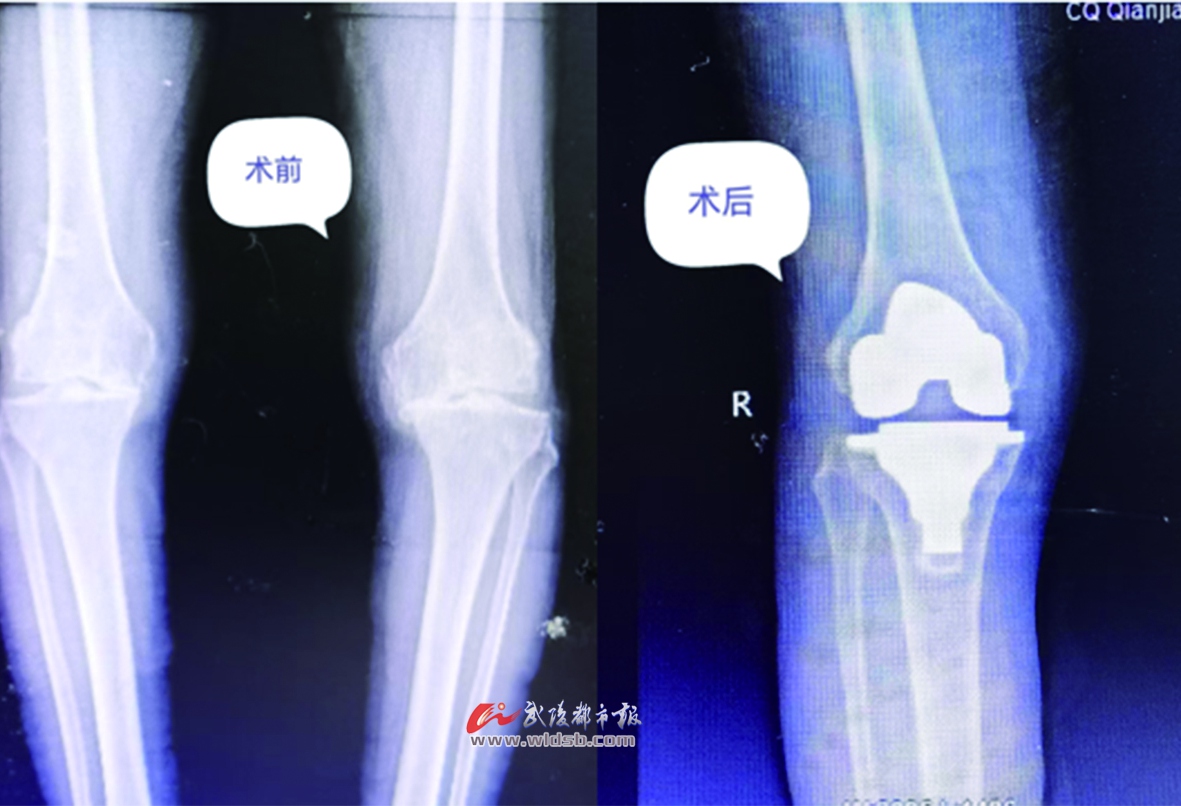

區中醫院骨科主任楊光海介紹,結合影像學診斷,病人膝關節內側間隙已經完全消失,提示軟骨已經磨損得非常嚴重,導致關節間隙變窄,屬于骨關節炎的終末期。

由于老人病程較長,此時的情況已較為嚴重。區中醫院骨科救治團隊綜合考慮分析后,決定為簡婆婆實施人工膝關節表面置換術。簡單來說,就是將磨損膝關節軟骨去除,安裝固定人工假體,從而糾正患者膝關節的畸形和下肢力線,達到治療的目的。

術前術后對比